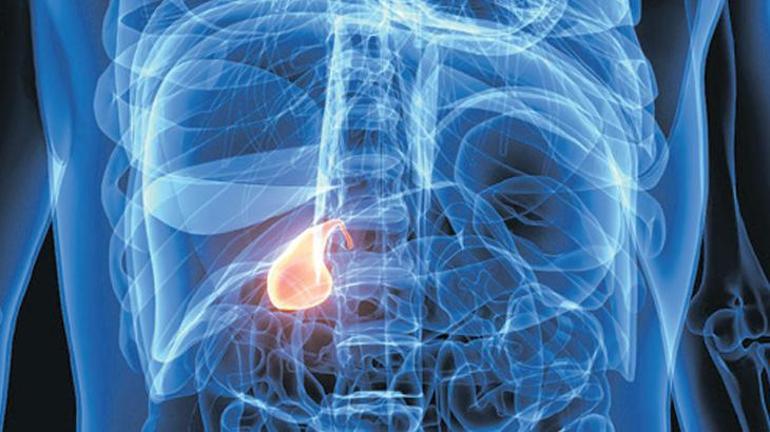

Didem Seymen / HABER MERKEZİ – Hızlı kilo kaybı sağlayan zayıflama iğnelerinin, safra kesesi hastalıklarını ve sindirim sistemi sorunlarını tetikleyebileceği ifade ediliyor. Prof. Dr. Mehmet Karabulut’a göre zayıflama iğneleriyle safra kesesi taşı riski, çoğu zaman ilacın doğrudan etkisinden çok kilo kaybının hızına bağlı gelişiyor. Karabulut, klinik çalışmalarda GLP-1 grubu ilaç kullanan kişilerde safra kesesi sorunlarının yüzde 1 ila 3 oranında görüldüğünü belirtiyor.

Ancak kısa sürede vücut ağırlığının yüzde 10-15’inden fazlasını kaybeden kişilerde bu riskin yüzde 10-20 seviyelerine kadar çıkabildiğini ifade ediyor. Daha önce safra taşı veya safra çamuru öyküsü olan kişilerde ise riskin yüzde 20’nin üzerine çıkabileceğini vurguluyor. Karabulut’a göre hızlı kilo kaybı safra kesesinin yeterince boşalamamasına ve safranın yoğunlaşmasına yol açarak taş oluşumunu kolaylaştırıyor. Bu nedenle tedavi sürecinin kontrollü yürütülmesi, uygun hasta seçimi ve düzenli doktor takibinin önemli olduğuna dikkat çekiyor.

Prof. Dr. Erhun Eyüboğlu, safra taşı oluşumunun yalnızca zayıflama iğnelerine özgü olmadığını, obezite cerrahisi sonrası da hastalarda sorunların görülebildiğini söylüyor. Tirzepatid etken maddeli iğnede doz artışı ile taş oluşum riski de artıyor. Ancak bu oran yüzde 0.6 civarında. Eyüboğlu’na göre, hızlı kilo kaybı sırasında safra içinde kolesterol yoğunluğu artıyor ve bu durum safra çamuru ile taş oluşumuna zemin hazırlıyor. Ayrıca aşırı kalori kısıtlaması safra kesesi kasılmalarını azaltarak safra durgunluğuna yol açabiliyor. Haftada 1.5 kilodan fazla kilo veren kişilerde safra taşı oluşumunun daha sık görüldüğünü belirten Eyüboğlu, riskin kilo kaybının en hızlı olduğu ilk 20 haftada belirginleştiğini, kilo verme hızının yavaşlamasıyla riskin azaldığını söylüyor.

Doç. Dr. Erkan Yardımcı’ya göre hızlı kilo kaybı sırasında yağ dokusundan kana ve oradan safraya yoğun kolesterol geçişi oluyor. Safra kesesinin kasılma hareketlerinin azalmasıyla birlikte oluşan safra çamuru zamanla taşlara dönüşebiliyor. Bu durumun bazen akut pankreatite yol açabileceğini belirten Yardımcı, pankreatitin hayatı tehdit eden ciddi bir tablo olabileceğine dikkat çekiyor. Bazı çalışmalarda GLP-1 agonistleri kullanan kişilerde pankreatit riskinin her 100 kişide 1 kişi olduğu belirtiliyor. Ancak bu durumun doğrudan ilaç etkisinden mi yoksa kilo kaybının kendisinden mi kaynaklandığının henüz net olmadığı vurgulanıyor.